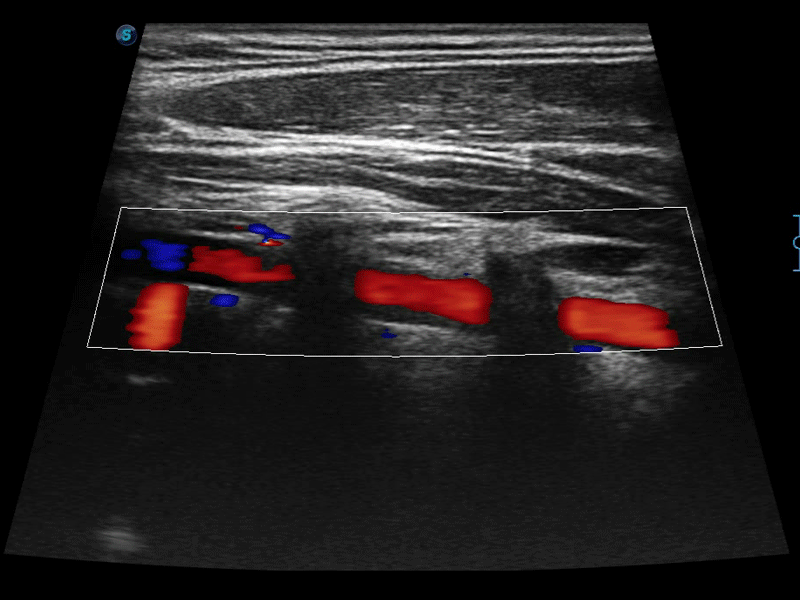

高分辨率血流成像技术提高了对低速血流信号的检测能力。在提高空间分辨率的同时,也克服了血流外溢现象,为用户提供更加真实的血流动力学信息。